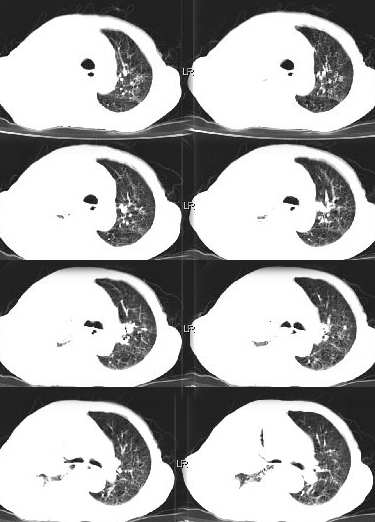

男,76岁,因心累,气紧加重,伴吐白色沫哝痰,偶尔有低烧,无盗汗。{门诊患者未见其它检查}

病灶在右上叶支气管的后段旁,成类圆形,约2.3厘米大小,其内见钙化密度区,病灶平扫为77,强化为87.左肺上叶尖后段沿血管支气管分布见小结节.我认为右上叶后段支气管开口有截断.我首先考虑是右中央型肺癌伴右恻大量胸腔积液,但左肺的病变我真的有的不好解释,希望各位战友继续讨论,不对之处望指出!!谢谢!!!

右肺毁损萎陷,其内可见钙化灶、残存空腔及支气管影。左上叶可见多发小结节影。纵隔左移,其内未见肿大淋巴结。右侧胸腔大量积液。考虑:肺结核并右肺毁损;右侧胸腔大量积液。

右侧大量胸腔积液伴右肺压迫性肺不张,上叶内是不是结核灶?

右侧大量胸腔积液伴右肺压迫性肺不张,左上叶结核.

右肺萎陷,上叶似有肿块,其内见条状、点状钙化,上叶后段支气管有阻塞征象,纵隔内见肿大淋巴结影,右侧大量胸水,陈旧性结核。同时不排除在原有双肺结核的基础上出现右上肺癌并胸膜及纵隔淋巴转移的可能

右上叶后段开口处可见约3cm·3cm大小的肿块,边缘较光滑,无明显分叶且有钙化,右上叶支气管后壁受侵不明显,加上左上叶病灶。我首先考虑肺结核,胸腔积液。右肺不张。还是建议支气管镜检查,或者胸水检查。

右后段处示一肿块但无明显肺癌强化方式,其内尚见钙化,胸膜亦无结节样增厚,再加上左肺结核表现(支血束结节样增粗不确切),则更支持结核伴大量胸液表现。